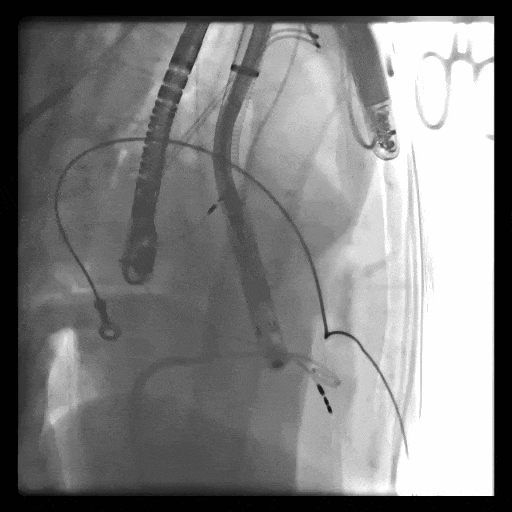

第一例患者手術難點

1、血管入路問題,最窄處平均徑5.5mm(小于8.5mm),輸送器存在進入受阻礙風險; 2、投照體位過大,RAO76°,術中影響輸送器操作可能性大;3、三尖瓣環大,同軸性難調整,易產生瓣周漏;4、起搏器導線在三尖瓣瓣環中心位置穿過,且較短,可能限制人工瓣膜展開,且尖端靠近室間隔錨定區,可能影響錨定;5、三尖瓣極重度反流,藥物不能緩解患者的癥狀,在應用LuX-Valve Plus之前,心臟專家經長時間評估均未為患者找到合適的產品或治療方案。

術中DSA顯示起搏器導線的干擾,右心室造影確定瓣環位置,操作空間小